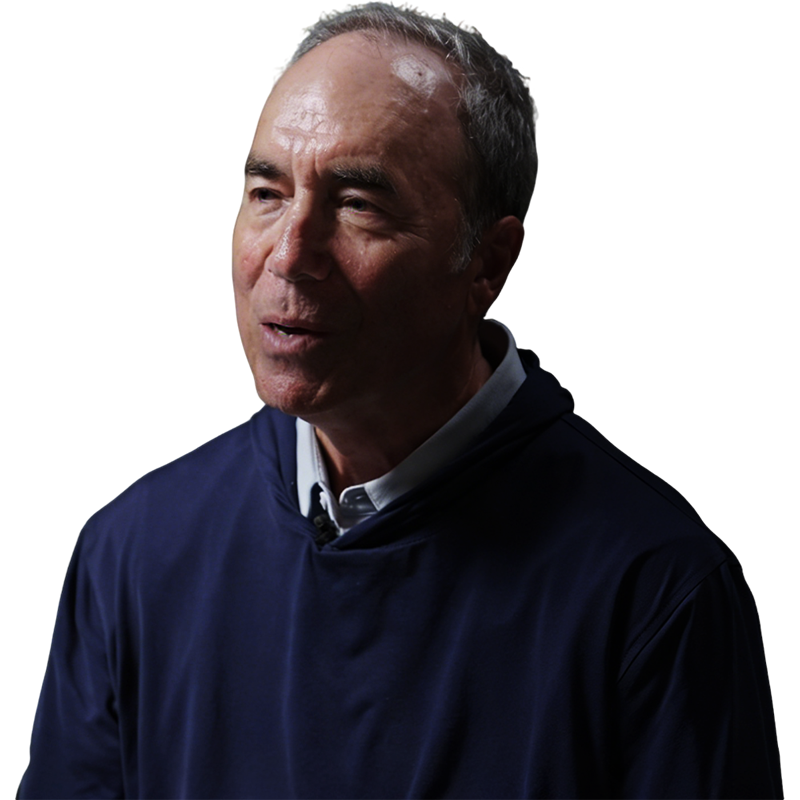

Fred Apple

Professor and Principal Researcher at the University of Minnesota

"Next-generation cardiac biomarkers can detect and predict disease, enabling us to intervene before injury occurs. "